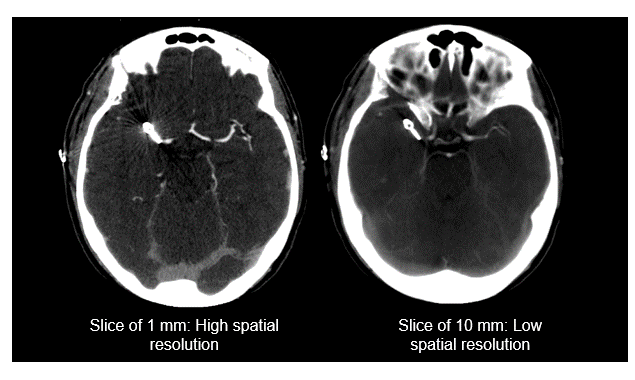

SR and Slice Thickness

Remember, a high spatial resolution is important for one to discriminate between structures that are located within proximity to each other.

The thickness of the slice also impacts spatial resolution. As shown in these two images, when the slice thickness is larger the spatial resolution is lower. The thicker the slices the less the detail in the image. Large slice thicknesses reduce spatial resolution in the cranial-caudal axis; they also reduce the sharpness of edges of structures in the transaxial image.